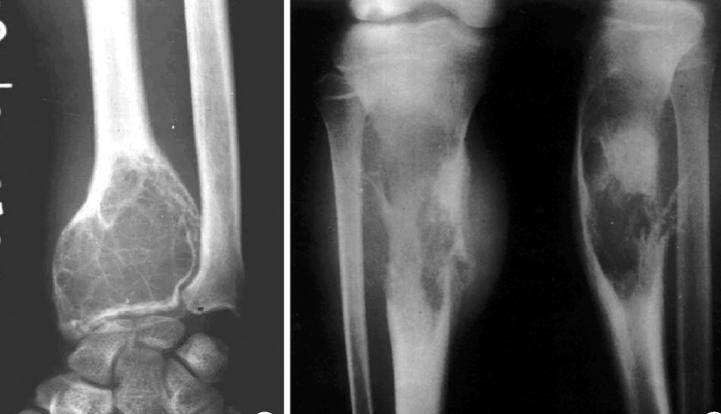

1.初步检查:先做X线检查,可观察骨骼破坏情况,能发现骨肉瘤特征性的“Codman三角”或“日光射线”状骨针表现。

2.详细检查:通过CT和MRI明确肿瘤的范围、大小,以及和周围神经、血管的关系,为手术方案制定提供依据。